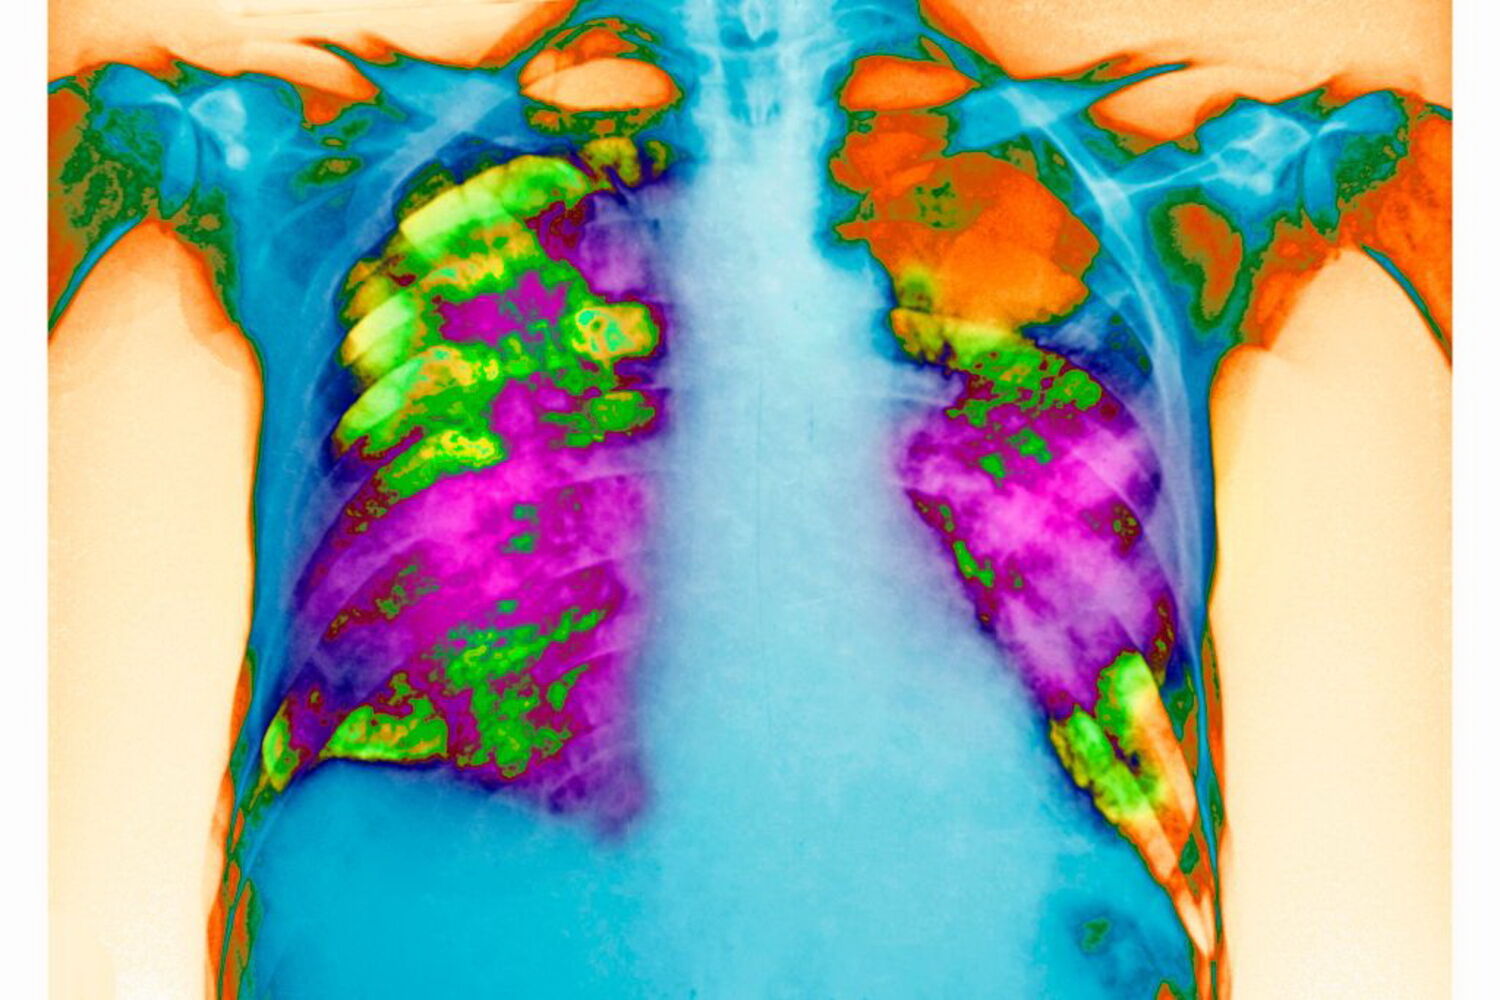

O que é a pneumonia?

A pneumonia é causada por bactérias, vírus ou fungos. Conheça os sintomas.

A pneumonia consiste numa inflamação aguda do tecido pulmonar, em particular dos alvéolos, os "sacos de ar" do pulmão. Devido à inflamação, ficam preenchidos com líquido não conseguindo realizar as trocas gasosas em que consiste a respiração.